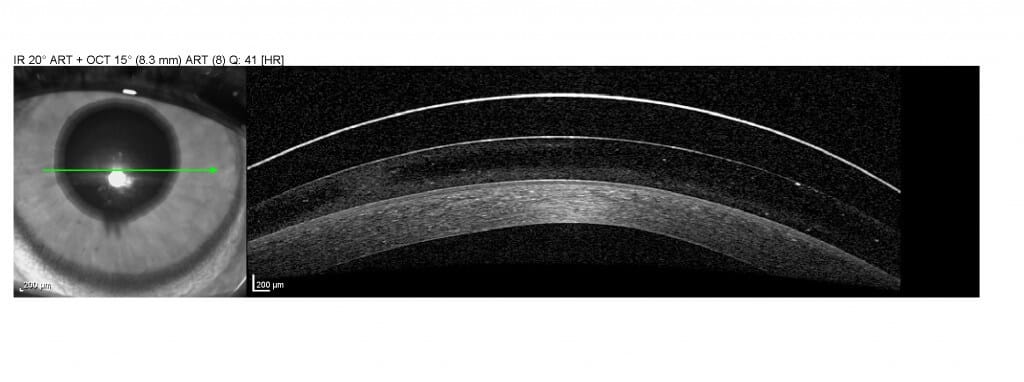

תמונת OCT של עין עם עדשה סקלרלית. בחלק העליון של התמונה ניתן לראות את העדשה, הנוזל הנמצא בין העדשה לקרנית ובחלק התחתון הקרנית.